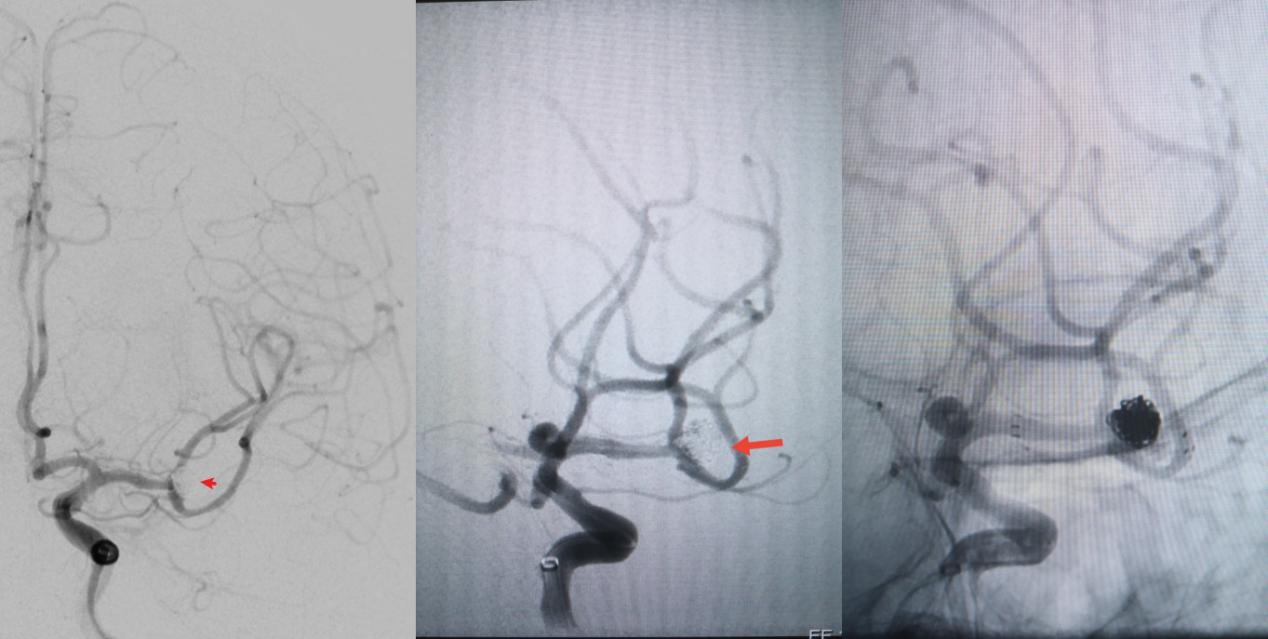

病例一为77岁女性患者,既往高血压病史。因“突发剧烈头痛伴恶心2天”前来清华大学附属垂杨柳医院急诊科就诊。头颅CT检查提示蛛网膜下腔出血,头颈动脉CTA提示右侧大脑中动脉M1段分叉处宽颈动脉瘤。神经外科脑血管病介入团队急诊为患者实施了全脑血管造影术(DSA),造影显示动脉瘤不规则,可见子囊,宽颈,主要累及下干。团队采取了支架辅助弹簧圈栓塞术,患者颅内“不定时炸弹”被成功拆除。动脉瘤达到致密栓塞,载瘤动脉通畅。住院半个月后顺利出院,无神经功能障碍。

▲术前DSA显示宽颈动脉瘤,有子囊,主要累及下干

▲术后DSA显示动脉瘤致密栓塞,载瘤动脉通畅

病例二为58岁女性患者。因“突发剧烈头痛伴呕吐3小时”就诊于清华大学附属垂杨柳医院急诊科,行头颅CT检查提示蛛网膜下腔出血。患者嗜睡,频繁呕吐,不排除颅内再出血。为争分夺秒抢救患者生命,神经外科脑血管病介入团队紧急为患者实施了DSA,显示左侧大脑中动脉分叉处宽颈动脉瘤,主要累及下干。术中采取双微导管技术,于动脉瘤内填塞弹簧圈,并置入一枚支架保证致密栓塞和下干分支血管的通畅。成功“拆弹”,化险为夷,患者恢复过程顺利,出院时无神经功能缺损。

▲术前DSA显示左侧大脑中动脉分叉宽颈动脉瘤,可见子瘤,主要累及下干